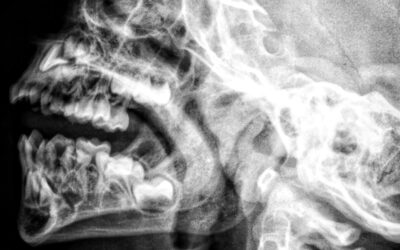

Ce înseamnă, când este necesar și ce beneficii oferă Ce este sinus lift-ul? (ridicarea sinusului maxilar) Sinus lift-ul, cunoscut și ca ridicarea sinusului maxilar, este o procedură de augmentare osoasă necesară atunci când osul din zona premolarilor și molarilor...

Știai că un dinte infectat poate provoca o infecție de sinus… și că o sinuzită netratată poate da, la rândul ei, dureri la nivelul dinților?Asta pentru că rădăcinile măselelor superioare sunt extrem de aproape de sinusurile maxilare – uneori chiar la câțiva milimetri....